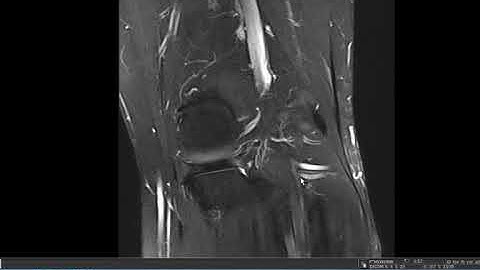

How to Read an MRI of the Knee for Beginners